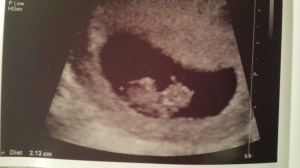

Things are a-changin’ around the Evans’ household, and Isla is getting a big promotion come June 2015:

Baby Evans #2 is due June 24, 2015, and we couldn’t be more excited!

The Cashew at 8 weeks